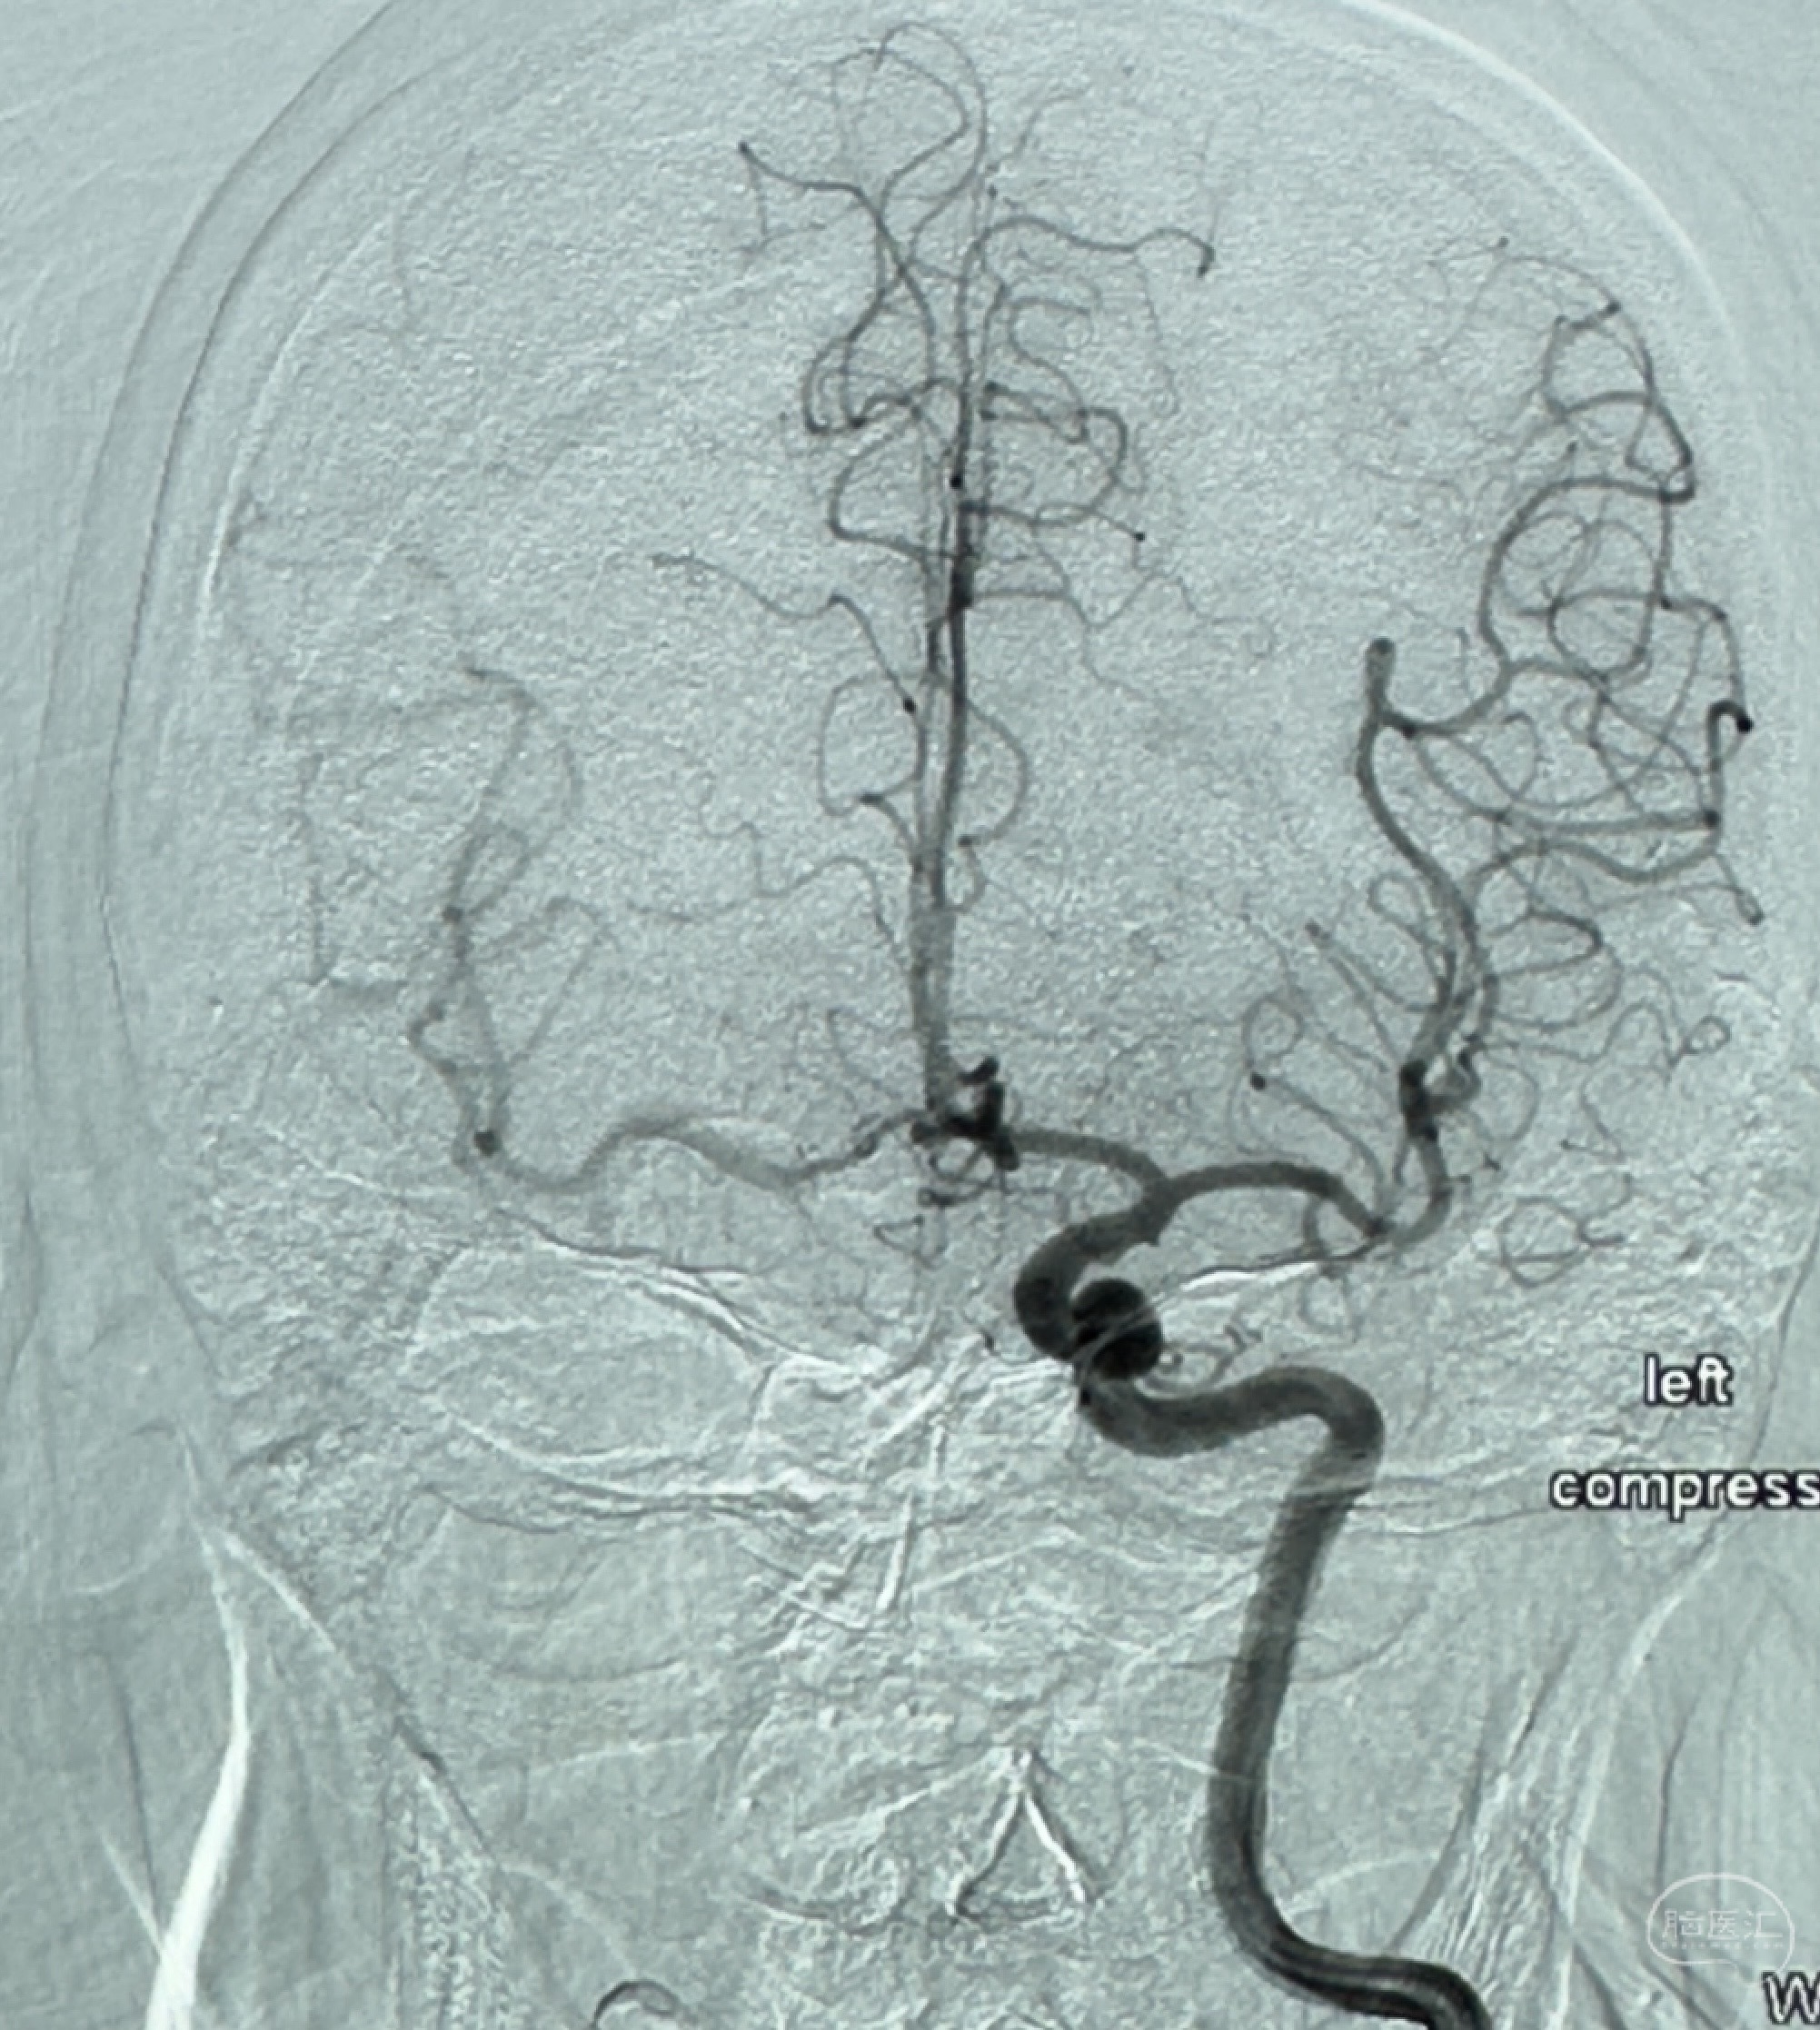

2023-12-08外院DSA:右侧颈眼动脉瘤,约13*12mm大小,压颈试验显示左右向及后向前代偿可

2023-12-27术后第十天复查DSA

支架贴壁佳,但可见射流,咋办?